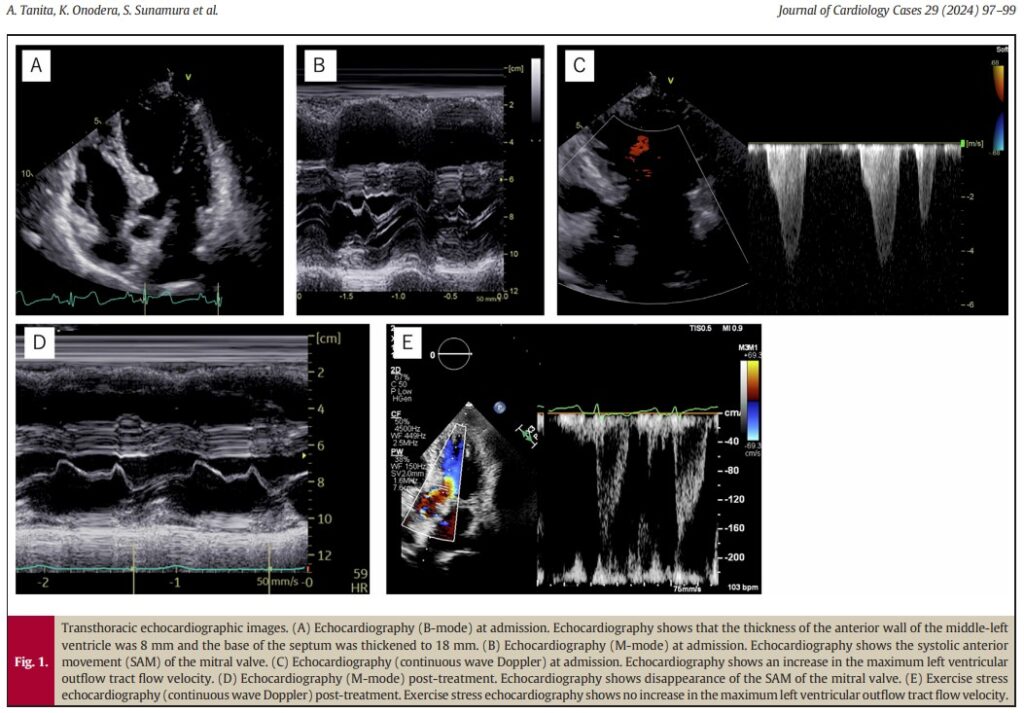

Mulher, 73 anos de idade, admitida no pronto socorro após síncope durante esforço físico. Ao exame, notava-se sopro sistólico em foco aórtico (3+) e ecocardiograma documentava a presença de hipertrofia de 18 mm confinada à região basal do septo interventricular.

A espessura diastólica dos demais segmentos do septo interventricular e da parede posterior era de 8 mm e a velocidade de pico na via de saída do ventrículo esquerdo era de 4.3 m/s, com gradiente máximo de 74.2 mmHg. Havia também refluxo valvar mitral moderado secundário à presença de movimento sistólico anterior (SAM) da valva mitral.

Foi iniciada terapia com bisoprolol 1.25 mg/dia com melhora sintomática e desaparecimento do SAM (figura D). A velocidade máxima da via de saída do ventrículo esquerdo, observada em avaliação posterior, foi de 1.5 m/s, com gradiente de pico de 7.4 mmHg. Um ecocardiograma com estresse físico foi realizado, com boa resposta durante o esforço e ausência de sintomas.

Ainda, a paciente foi submetida a estudo com ressonância magnética cardíaca para descartar a presença do septo sigmoide como parte de um fenótipo de CMPH. O resultado, contudo, não demonstrou fibrose miocárdica.